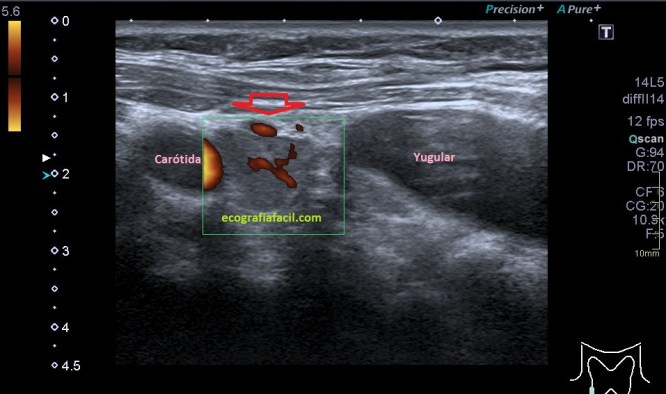

Varicocele: Estrella invitada de muchas exploraciones de escroto que llegan a la sala. Por eso lo he dejado para el final. Es la colección de venas agrandadas, tortuosas y anormalmente dilatadas.

En la imagen 15 puedes ver una imagen bastante sugerente de varicocele, en esos vasos anecoicos e hipocogénicos podemos encontrarnos un movimiento lento de la circulación sanguínea visible sin necesidad de doppler en relajación, pero que cambia su aspecto con el modo doppler y/o modo angio y con maniobra de valsalva como ves en la imagen 16. Hay diferentes grados, nosotros debemos documentar todo de manera correcta para que la radióloga pueda evaluar y definir el nivel o grado de dicho varicocele.